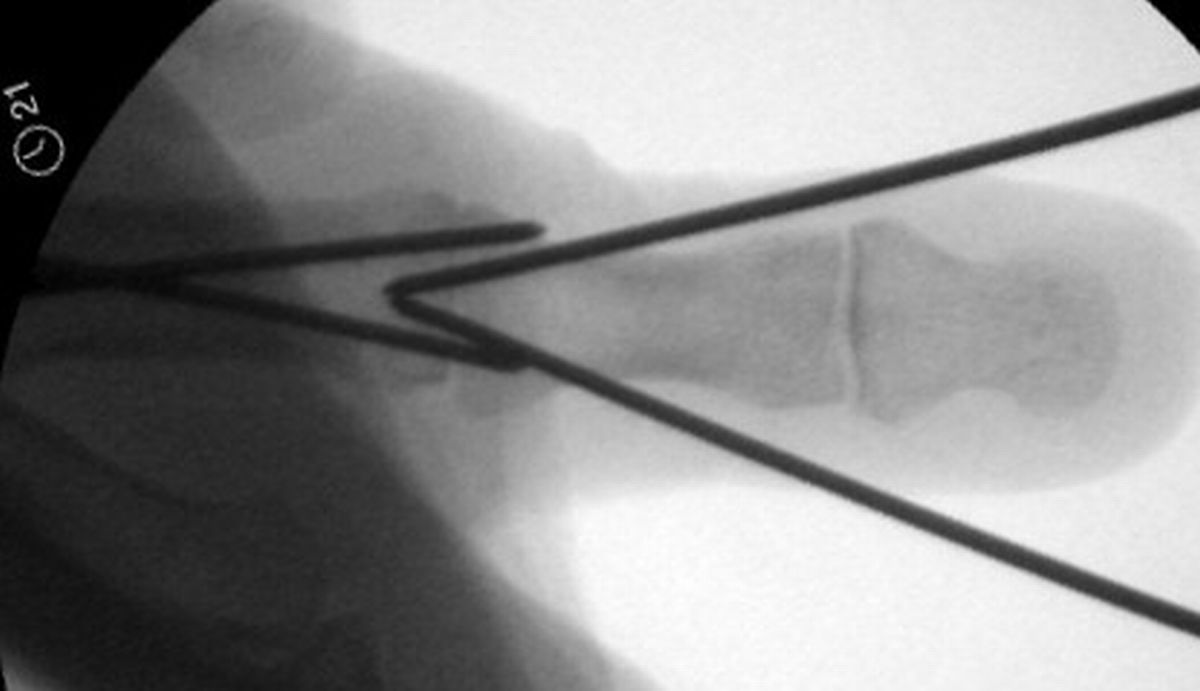

| These were then replaced,

one at a time, with 1.5mm screws. Because of the entry angles, the

countersink bit was used to reduce screw head prominence. |

| Final Result |